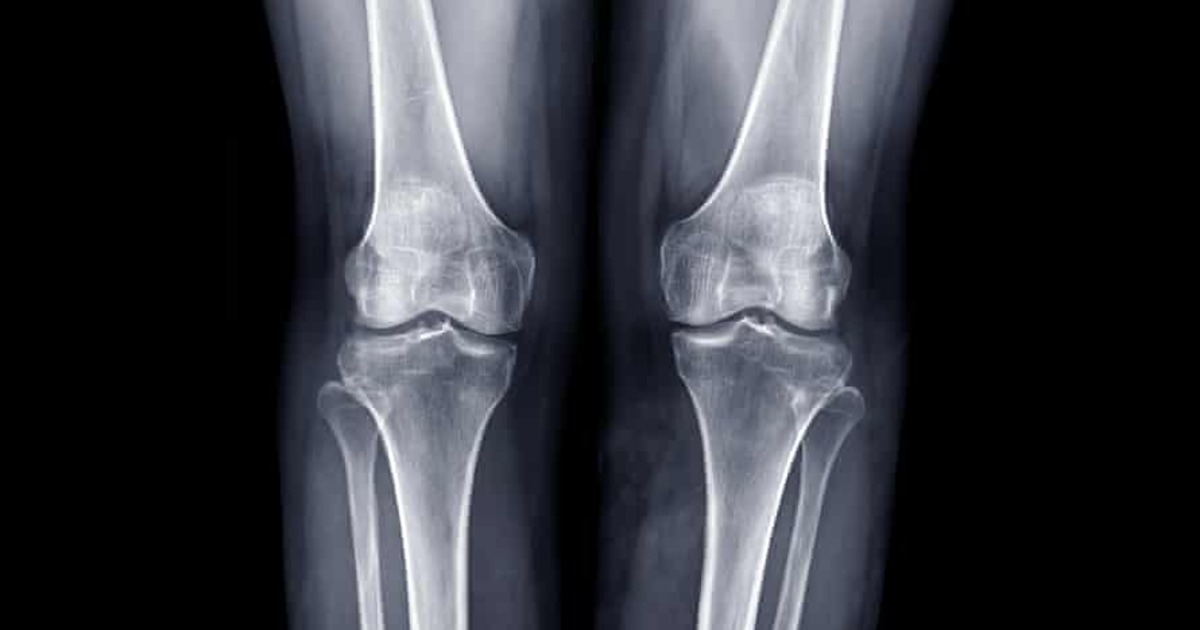

На данный момент, пишет автор материала, наиболее эффективный способ лечения дефектов костей — трансплантация костной ткани самого пациента. Но она имеет нежелательные и неприятные для человека последствия. Например, кровопотеря, болезненные ощущения, гематомы.

Созданная учёными разработка решит эту проблему. Более того, костная ткань при использовании нового метода будет сформирована ещё быстрее. В его основе — технология генной терапии.